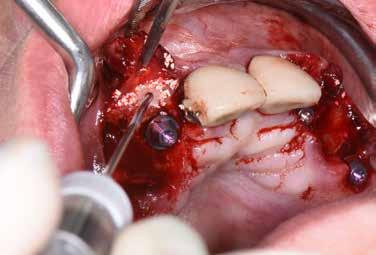

kális fertőzés a műtét helyén, valamint korábbi GBR/BTR kezelés a fogeltávolítás helyén Betegenként minimum egy egy-gyökerű fog kutatásba való bevétele történt meg (1 ábra) Minden kutatásba bevont beteget két független parodontológus vizsgált meg, hogy megbizonyosodjon arról, az eltávolítandó fogak reménytelen prognózisúak Standardizált intraorális röntgenfelvételek (2. ábra) és CBCT- felvételek (3. a-b ábra) készültek a vizsgálati helyen� A CBCT-felvételeken a keményszöveti- és alveoláris dimenziók preoperatíve megmérésre kerültek Összesen kilenc, reménytelen prognózisú (két független klinikus által igazolt) fog került eltávolításra helyi érzéstelenítésben, 4%-os epinefrin és 1:100000 arányú adrenalin segítségével Az extrakciókat fogó, és szükség esetén emelő kíméletes alkalmazásával végezték� Az extrakciós üregek tisztítása lebeny nélküli megközelítéssel történt Lucas-féle kanalakkal és szikével A bukkális dehiszcencia mértékét és az EDS besorolást közvetlen klinikai mérésekkel, PCP-UNC 15 parodontális szondákkal igazolták Azon betegek kerültek bevonásra a studyba, akik EDS 3-4-es

4 ábra: (a) Az alveoláris gerinc prezervációját fertőtlenített ATB-grafttal végezték (BonMaker®, Korea Dental, Solutions Co. Ltd., Dél-Korea), (b) foghúzást követően FGG graftokkal lettek az üregek fedve.

A fertőtlenítési és előkészítési procedúra lezajlása után az extrakciós üregeket feltöltötték ATB-porral (4. a ábra), (szemcseméret: 425 µm–1500 µm közötti)� Az optimális lágyszöveti fedés és a beültetett helyek zavartalan gyógyulásának biztosítása érdekében a 6 hónapos gyógyulás során a szájpadlásról vagy a maxilla tuber-területéről nyert szabad ínygraftokat nyertek ki, melyeket 6/0-s, nem felszívódó varratokkal illesztettek a fogeltávolítás helyére (Dafilon, Braun B Melsungen, Tuttlingen, Németország), (4. b ábra)

A műtétet megelőzően és azt követően standardizált, intraorális röntgenfelvételek készültek a vizsgált helyeken A varratszedésre 14 nappal a műtétet követően került sor A lágyszövetek kvalitatív értékelését a műtétet követően 1, 3 és 6 hónap elteltével végezték el (5. ábra) A keményszöveti változások radiológiai vizsgálata céljából, hat hónappal a fogeltávolítást követően, standardizált, intraorális röntgenfelvételeket és CBCT-vizsgálatokat (6. a-b ábra) végeztek az érintett helyeken az újra feltárás és az implantáció előtt Az újra feltárást helyi érzéstelenítésben végezték (7. a. ábra) Az újra képződött keményszövet mennyisége a műtét előtt végzett CBCT-felvételen került kiértékelésre Az implantáció helyén 2,6 mm belső/3,6 mm külső átmérőjű trepánfúróval (7. b ábra), (Komet Dental, Lemgo, Németország) szövettani mintavétel (core-biopszia) történt 10 mm mélységben, az implantátum beültetését megelőzően, a tervezett implantátumpozíció hossztengelyében Ezt követően történt meg az implantátumok behelyezése (ICX, Medentis Medical GmbH, Németország), (8. a-b ábra) a core-biopsziás mintavétel helyére, az implantátumrendszer saját fúróival végzett csontfészek-kialakítás után Ha a behelyezést követően az implantátumnak maradt szabadon menetes felszíne, egyidejűleg GBR-műtét elvégzése is történt autogén csont- és xenogén graftanyagok kombinációjával (cerabone®, botiss, Németország) A kompozit-graftot felszívódó membránnal fedték (Jason®, Botiss, Németország), és titánszegekkel vagy varratokkal rögzítették a csonthártyához

A kezdeti sebgyógyulás eseménytelen volt, a teljes 6 hónapos gyógyulási időszak alatt nem volt jele graftexpozíciónak Az újonnan képződött, keratinizált szövetek minősége 1, 3 és 6 hónap múlva is kedvező volt, minden esetben lehetővé téve az optimális esztétikai implantációs rehabilitációt� Az újra feltáráskor a xenogén graftok általános viselkedésével ellentétben, az ATB-vel prezervált helyeken nem mutatkoztak a graft kötőszöveti beágyazódásának jelei Ilyen módon a crestalis csontnívó minden esetben megtartott volt� Az implantátum behelyezése mind a 9 ATB-grafttal kezelt helyen lehetséges volt, valamennyi implantátum beágyazódott a keményszövetbe, a menetek teljes csontos fedésben voltak A kilenc esetből hétnél kis-

mértékű kontúr-augmentációt végeztek az implantációval egy időben, a bukkális szövetmennyiség minimális hiánya miatt Egy esetben az implantátum beültetését arcüreg-emeléssel kombinálták a fogeltávolítás után pneumatizálódott sinus maxilláris miatt Radiológiai elemzésre preoperatív és 6 hónapos posztoperatív CBCT-felvételeket készítettek (3. b. ábra, 6. a. ábra) Az alveólus-üregek középvonalbeli tengelyei manuálisan kerültek meghatározásra a midbukkális, oro-vesztibuláris keresztmetszetekben, CBCT-felvételeken A műtét előtti és a műtétet követő mérési adatok pontos összehasonlítását a processus alveoláris mindkét CBCT-felvételen felismerhető anatómiai tájékozódási pontjainak megfelelő, standardizált mérőpontokon végezték, az alveólus-üreg midbukkális metszetének síkjában A horizontális méréseket 3 szinten végezték el: az alveoláris üreg crestalis szintjében, a crestalis szint alatt 2 mm-rel, és a crestalis szint alatt 4 mm-